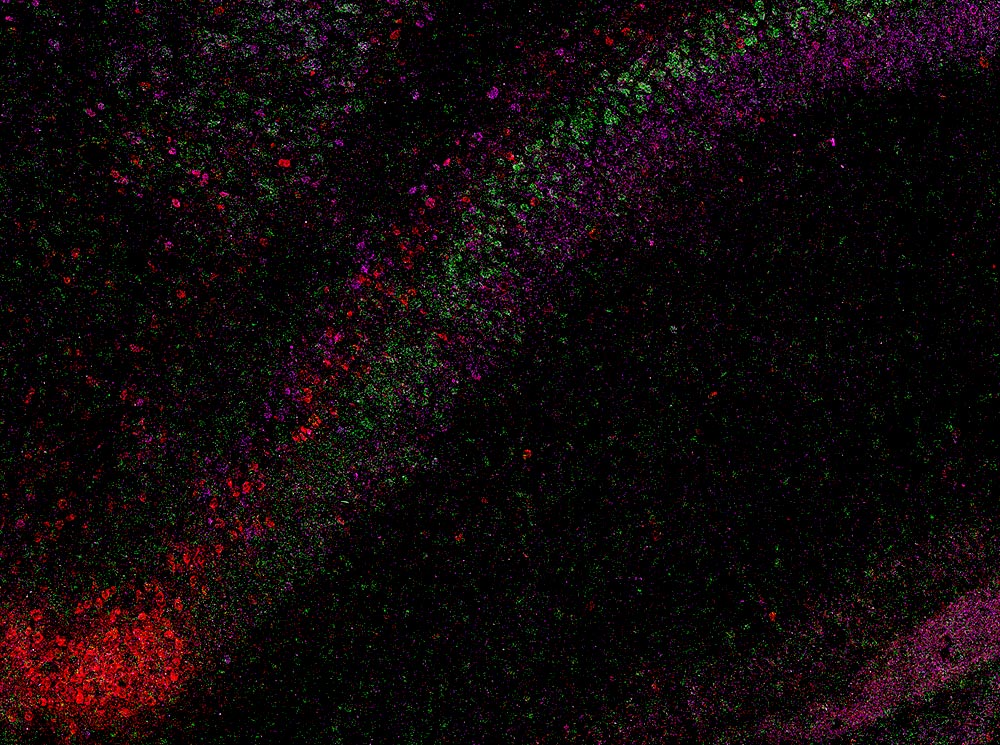

وللكشف عن هذا التنظيم الخفي، استخدم العلماء تقنية وسم الحمض النووي الريبوزي (RNA) تسمى RNAscope مع الفحص المجهري عالي الدقة. سمح لهم هذا المزيج برؤية جزيئات فردية من نشاط الجينات داخل خلايا CA1 الفأرية والتمييز بين أنواع الخلايا العصبية المختلفة بناءً على توقيعاتها الجينية. وفي إجمالي 58065 خلية هرمية CA1، حددوا أكثر من 330000 جزيء RNA، وهي الرسائل الجينية التي تشير إلى متى وأين تنشط الجينات. ومن خلال تتبع هذه الأنماط عبر الأنسجة، أنتج الفريق خريطة تفصيلية تحدد الحدود بين أنواع الخلايا العصبية المختلفة في جميع أنحاء منطقة CA1 في الحصين.

وأظهر التحليل أن CA1 ليس خليطًا فضفاضًا من الخلايا، ولكنه يتكون بدلاً من ذلك من أربع طبقات متواصلة من الخلايا العصبية، كل منها محددة بمجموعتها الخاصة من الجينات النشطة. عند النظر إليها بثلاثة أبعاد، تشكل الطبقات صفائح ممتدة تختلف قليلًا في سمكها وبنيتها، لأنها تمتد على طول الحصين. يساعد هذا الترتيب الواضح ذو النطاقات على التوفيق بين الدراسات السابقة التي أشارت إلى أن CA1 تم تنظيمه بشكل أشبه بمزيج تدريجي أو فسيفساء من أنواع الخلايا.

وقال ماريكارمن باتشيكانو، باحث الدكتوراه في معهد ستيفنز INI: “عندما تصورنا أنماط الحمض النووي الريبوزي الجيني بدقة الخلية الواحدة، تمكنا من رؤية خطوط واضحة، مثل الطبقات الجيولوجية في الصخور، يمثل كل منها نوعًا مميزًا من الخلايا العصبية”. مركز Connectomics التكاملية والمؤلف الأول المشارك لهذه الورقة. “إن الأمر يشبه رفع الحجاب عن البنية الداخلية للدماغ. قد تفسر هذه الطبقات المخفية الاختلافات في كيفية دعم دوائر الحصين للتعلم والذاكرة.”